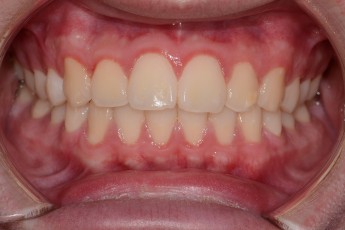

BEFORE & AFTER